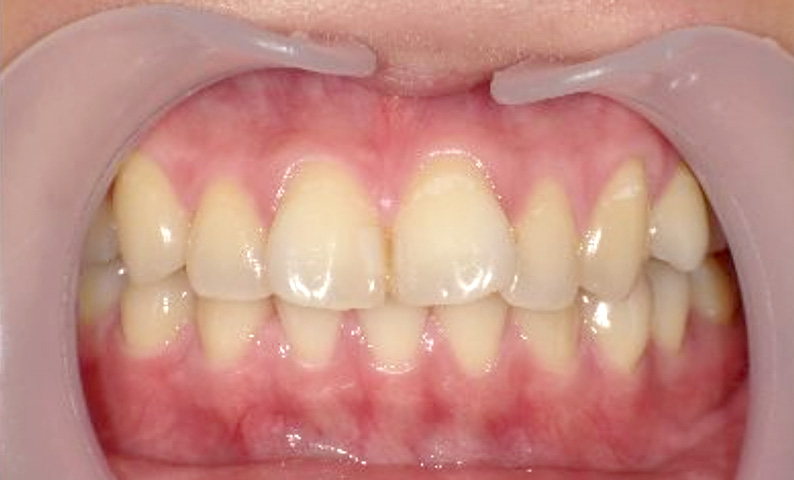

症例_025 上顎だけの部分矯正

治療期間:7ヶ月金額:30万円+税女性前歯のガタガタ上の前歯だけ

| Before | After |